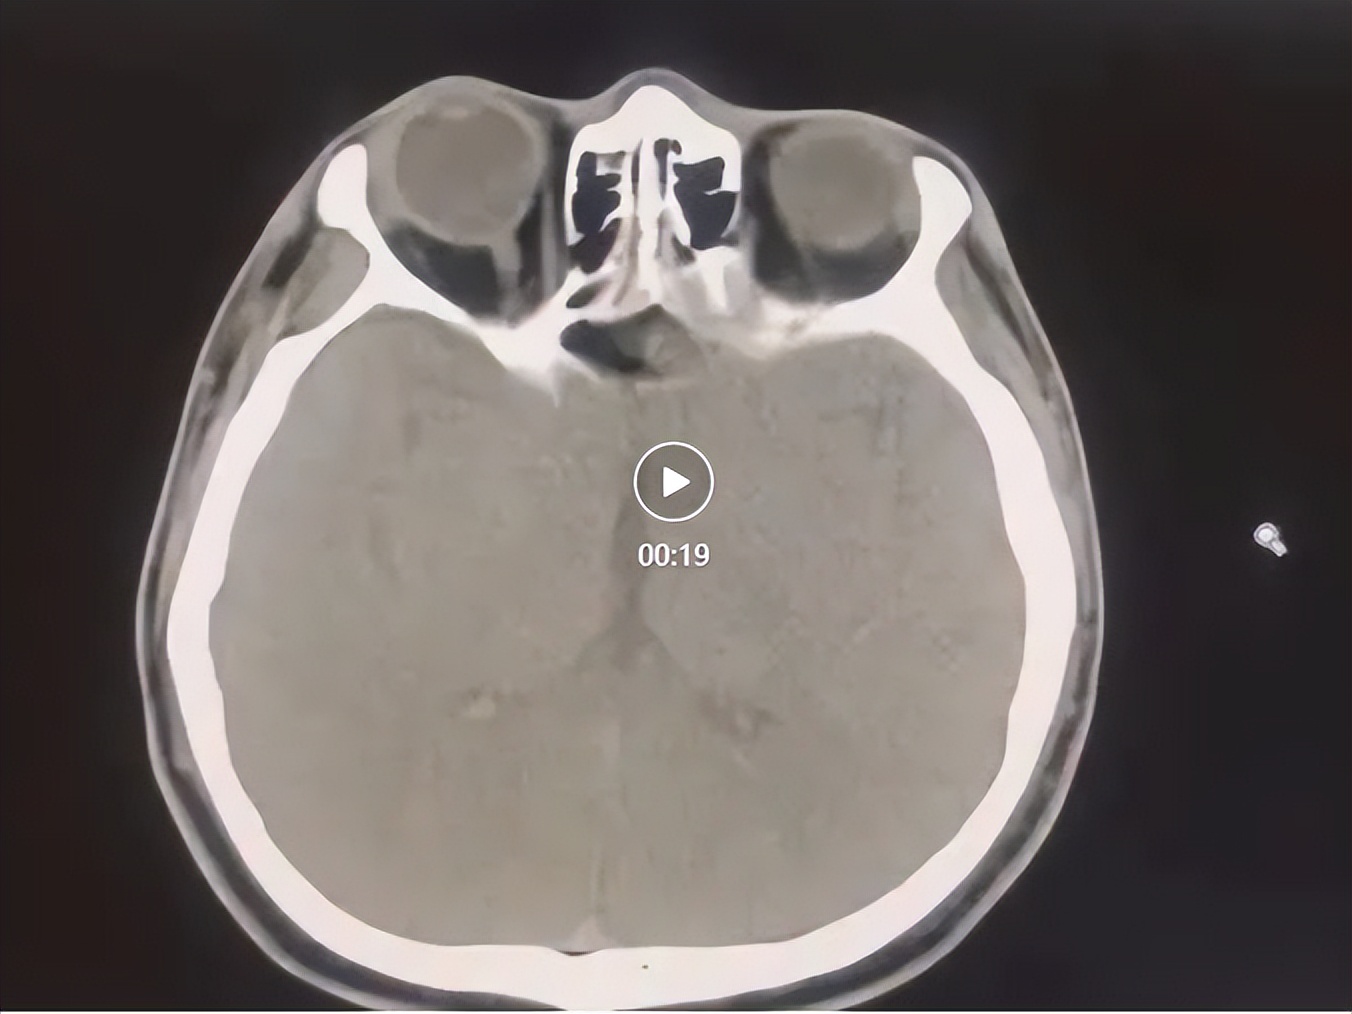

耳鼻喉科何平主治医师接诊后,对李先生进行了全面的体格检查,结合影像学检查,考虑为右侧颈部胸锁乳突肌深面囊性肿物,建议进行手术。